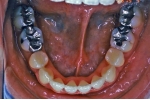

治療後5年経過時

|